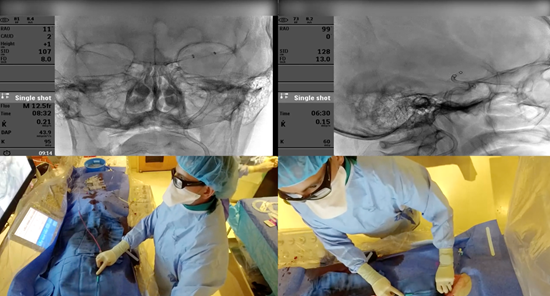

MEMORIAL BROADCASTS NEUROINTERVENTIONAL PROCEDURES TO GLOBAL AUDIENCES

Training Program Helps Doctors in Lower Income Countries

October 22, 2025 – While Memorial Neuroscience Institute (MNI) physicians save lives in South Florida using the latest neurointerventional procedures for brain aneurysms and strokes, they are also sharing clinical and technical expertise with doctors across the globe.

Memorial is one of only three programs in the U.S., and the only one in Florida, selected by the Society of Vascular and Interventional Neurology (SVIN) Mission Thrombectomy initiative to participate in its virtual fellowship for physicians in lower income countries. MNI was chosen for its excellent outcomes, rapid treatment workflow, and care coordination with Emergency Medical Services (EMS) in the community.